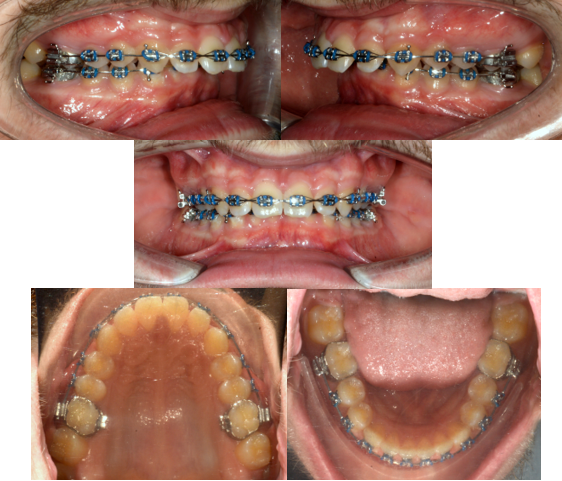

Kombinovaná ortodonticko chirurgická léčba: skeletální II. tř. (krátká dolní čelist) (chirurgická část terapie ve VFN Praha: prof. MUDr. R. Foltán, Ph.D.)

Začátek: výrazný předkus, krátká dolní čelist (zuby se vepředu "nepotkají", dolní čelist "nedosáhne dostatečně dopředu")

Ortodonticky připravené zubní oblouky před operací na čelistech

Konec: po zhojení následuje ortodontické doléčení a poté sejmutí fixního aparátu (zuby už se "potkají", dolní čelist "dosáhne dopředu")